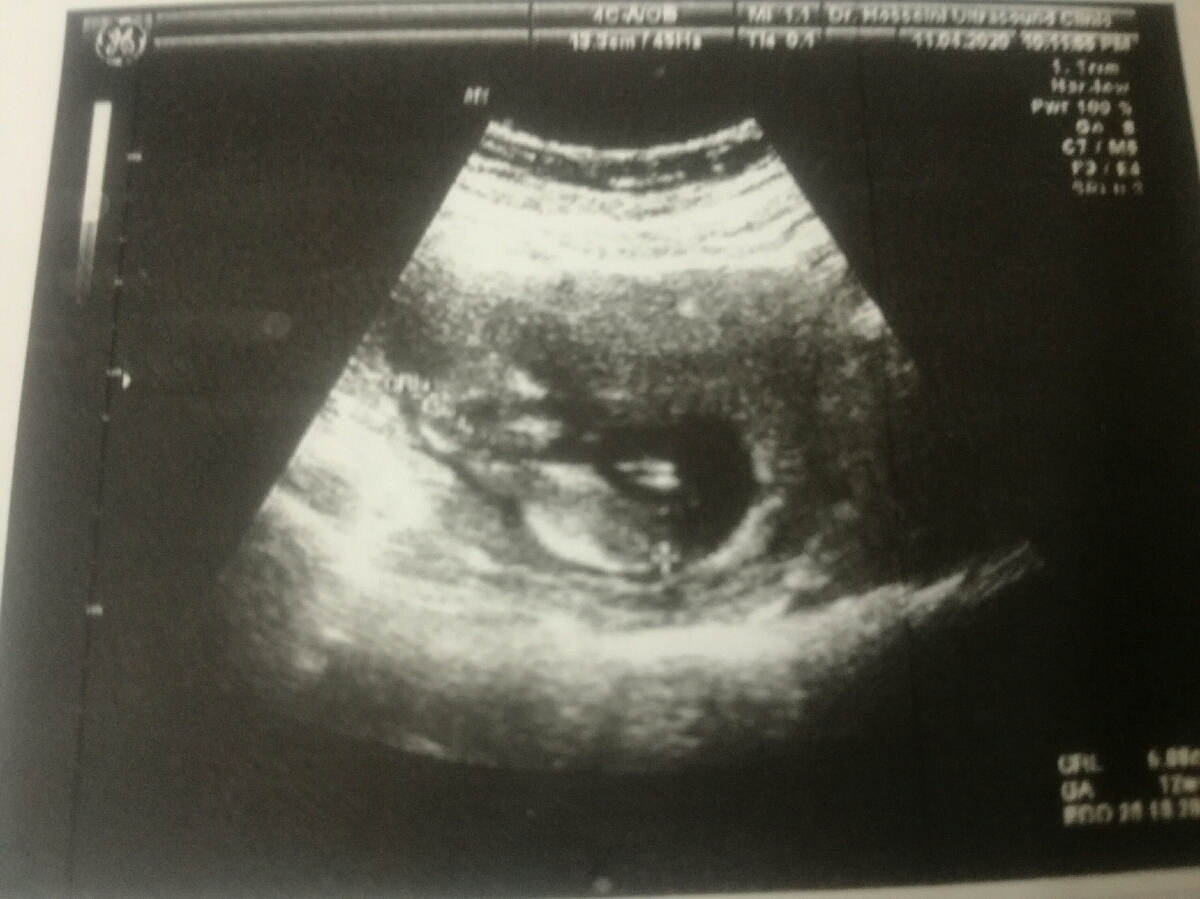

این ان تی عزیزم

بدتر از سونوگراف من چ بد عکس گرفته از بچه🤣🤣

سونوگراف تو خوب بوده عزیزم مال من اصلا مشخص نیس درست

سلام تعیین جنسیت آنومالی هفته شانزدهم به بعد قطعی است